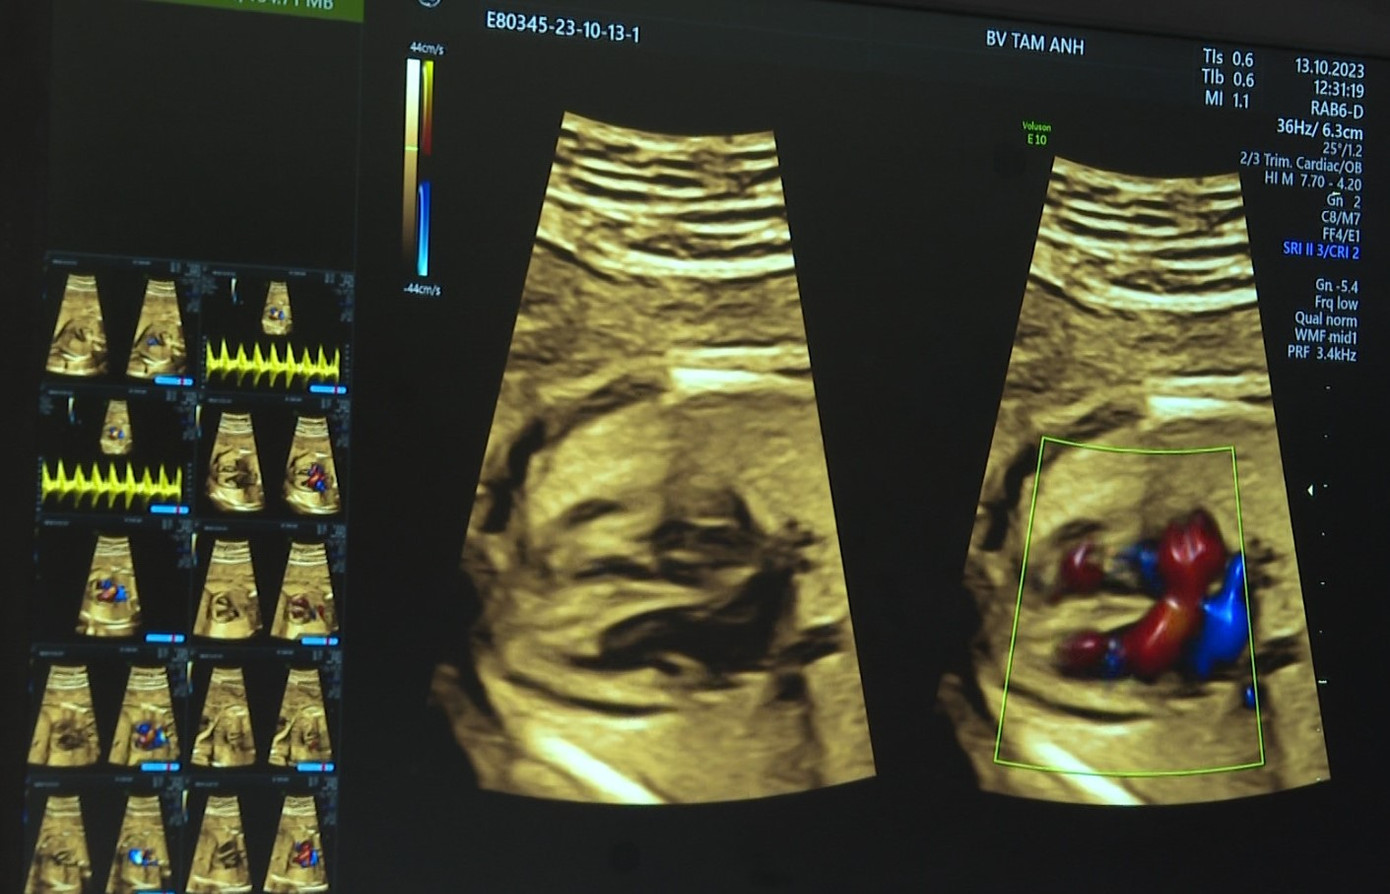

Từ cách siêu âm tim thai, tương quan hình thái/siêu âm tim thai, bệnh cơ tim thai nhi… được thực hiện trên máy siêu âm thế hệ mới chuyên dụng cho tầm soát bệnh lý tim bẩm sinh từ bào thai GE Voluson S8 Touch với phần mềm bản quyền ứng dụng trí tuệ nhân tạo. Nhờ hiệu ứng 3D của Doppler tự động phân tách từng mạch máu trong những tổ hợp mạch máu phức tạp, bác sĩ nhanh chóng phát hiện các bất thường về mạch máu như thông liên thất, hồi lưu tĩnh mạch phổi, chuyển vị đại động mạch, hẹp động mạch phổi… trên những quả tim nhỏ như đồng xu.

| Siêu âm cấu trúc tim thai được phân tích bởi công nghệ AI |